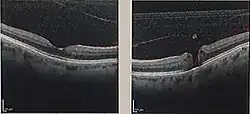

| Optical coherence tomography (OCT) of a macular hole (right) as compared to a normal macula. | |

A macular hole is a small break in the macula, located in the center of the eye's light-sensitive tissue called the retina.